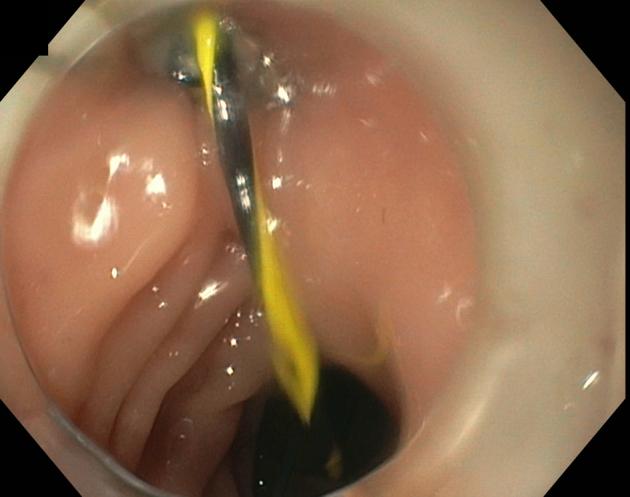

In this video case series, 3 cases of CVF patients treated endoscopically are presented to demonstrate the use of the currently available tools and techniques. The strategy used for the closure of the 3 CVFs was dependent on the size and etiology of the fistulas.

These cases demonstrate the use of the cap to perform vaginal endoscopy; the use of the over-the-scope clips, covered stents, and endoscopic suturing; and how they can facilitate the closure of fistulas in patients who are poor surgical candidates.